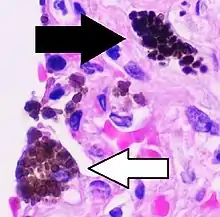

Cytology of a macrophage with typical features. Wright stain. | |